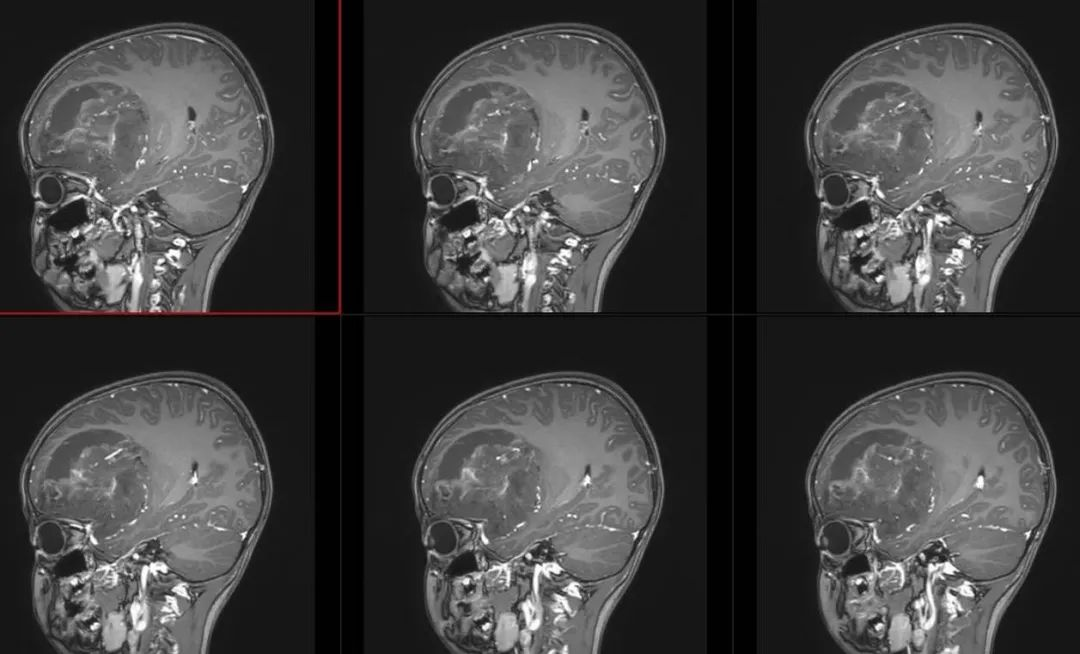

术前影像

术前T1轴位

术前T1冠状位

术前FLAIR

术前T2轴位

术前T2矢状位

术前颅脑MRA、MRV

术前T1冠状位增强

术前T1轴位增强